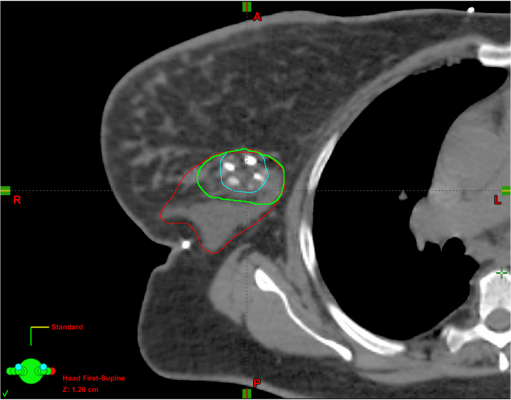

Does Ct Scan Show Breast Cancer : Radiological approach for malignant breast lesions - This can allow for examination of neighboring organs and structures like lymph nodes to check for any signs of disease.. If your doctor suspects that you have cancer near your abdomen, they may recommend an abdomen ct scan. With cancer cells, they appear as bright spots due to its higher metabolic rate compared to normal cells. Locally advanced breast cancer is stage iii. Right now, ct scans are not used routinely to evaluate the breast. Early breast cancer is stage i or ii.

Radiology by robots: this is what breast cancer looks like ... from www.ianmccafferty.com Once doctors know where to look, further evaluation can be done with other techniques. Should you get a ct scan to detect possible tumors? The stage shows how far the cancer has spread. Ct scan when a breast cancer has been diagnosed, some people have a ct scan of their chest and tummy (abdomen) to stage the breast cancer. If you have a large breast cancer, your doctor may order a ct scan to assess whether or not the cancer has moved into the chest wall. They may also use it to learn more about the cancer after they find it. With cancer cells, they appear as bright spots due to its higher metabolic rate compared to normal cells. Ct scans can detect bone and joint problems, like complex bone fractures and tumors.

PET/CT scan of a patient with breast cancer. A trace ... from www.researchgate.net Early breast cancer is stage i or ii. During the procedure, the patient is intravenously injected with a tracer containing sugar and radioactive material in small amounts. Pet/ct, which is a combination of positron emission tomography (pet) with. However, multidetector computed tomography (ct) often provides the first images of the breast when scanning is performed for pulmonary or cardiac disease. Ct scan when a breast cancer has been diagnosed, some people have a ct scan of their chest and tummy (abdomen) to stage the breast cancer. Knowing the stage helps your doctor decide which treatment you need. Then, this evening, after talking to mum about the scan appointment, i looked up great cancer and read about inflammatory breast cancer and that sure does fit the bill, perfectly. This test is most often used to look at the chest and/or belly (abdomen) to see if breast cancer has spread to other organs.

It is only with a pet/ct scan that you will know for sure. They may also use it to learn more about the cancer after they find it. However, multidetector computed tomography (ct) often provides the first images of the breast when scanning is performed for pulmonary or cardiac disease. Ct scan when a breast cancer has been diagnosed, some people have a ct scan of their chest and tummy (abdomen) to stage the breast cancer. Doctors often use ct scans to help them guide a needle to remove a small piece of tissue. A pet scan will help detect cancer and show how far it has spread. Metastases to the bone and brain also show up better on an mri. The pain starts in the rib area (where the breast ends) but goes. Key information about the cancer. This helps determine whether or not the cancer can be removed with mastectomy. This can allow for examination of neighboring organs and structures like lymph nodes to check for any signs of disease. Pet/ct, which is a combination of positron emission tomography (pet) with. Some cancers, such as prostate cancer, uterine cancer, and certain liver cancers, are pretty much invisible or very hard to detect on a ct scan.

Key information about the cancer. For the past few months i've been having left sided pain in the area just below my (non cancer side) breast. This helps determine whether or not the cancer can be removed with mastectomy. The grade indicates how fast the cancer is likely to grow. Pet scans are not used to screen women for breast cancer. Ct scan when a breast cancer has been diagnosed, some people have a ct scan of their chest and tummy (abdomen) to stage the breast cancer. Bone scans, positron emission tomography (pet), and computed tomography (ct) all continue to be employed alone or in combination for the detection of breast cancers suspected to have spread. Staging tells the doctor how big a cancer is and whether it has spread. Ct scans can detect bone and joint problems, like complex bone fractures and tumors. This test is most often used to look at the chest and/or belly (abdomen) to see if breast cancer has spread to other organs. In some cases, physicians use all three imaging techniques. This can allow for examination of neighboring organs and structures like lymph nodes to check for any signs of disease. The reality is that you cannot rely on a ct scan (or ultrasound, mri, or blood test) to tell you if you have cancer.